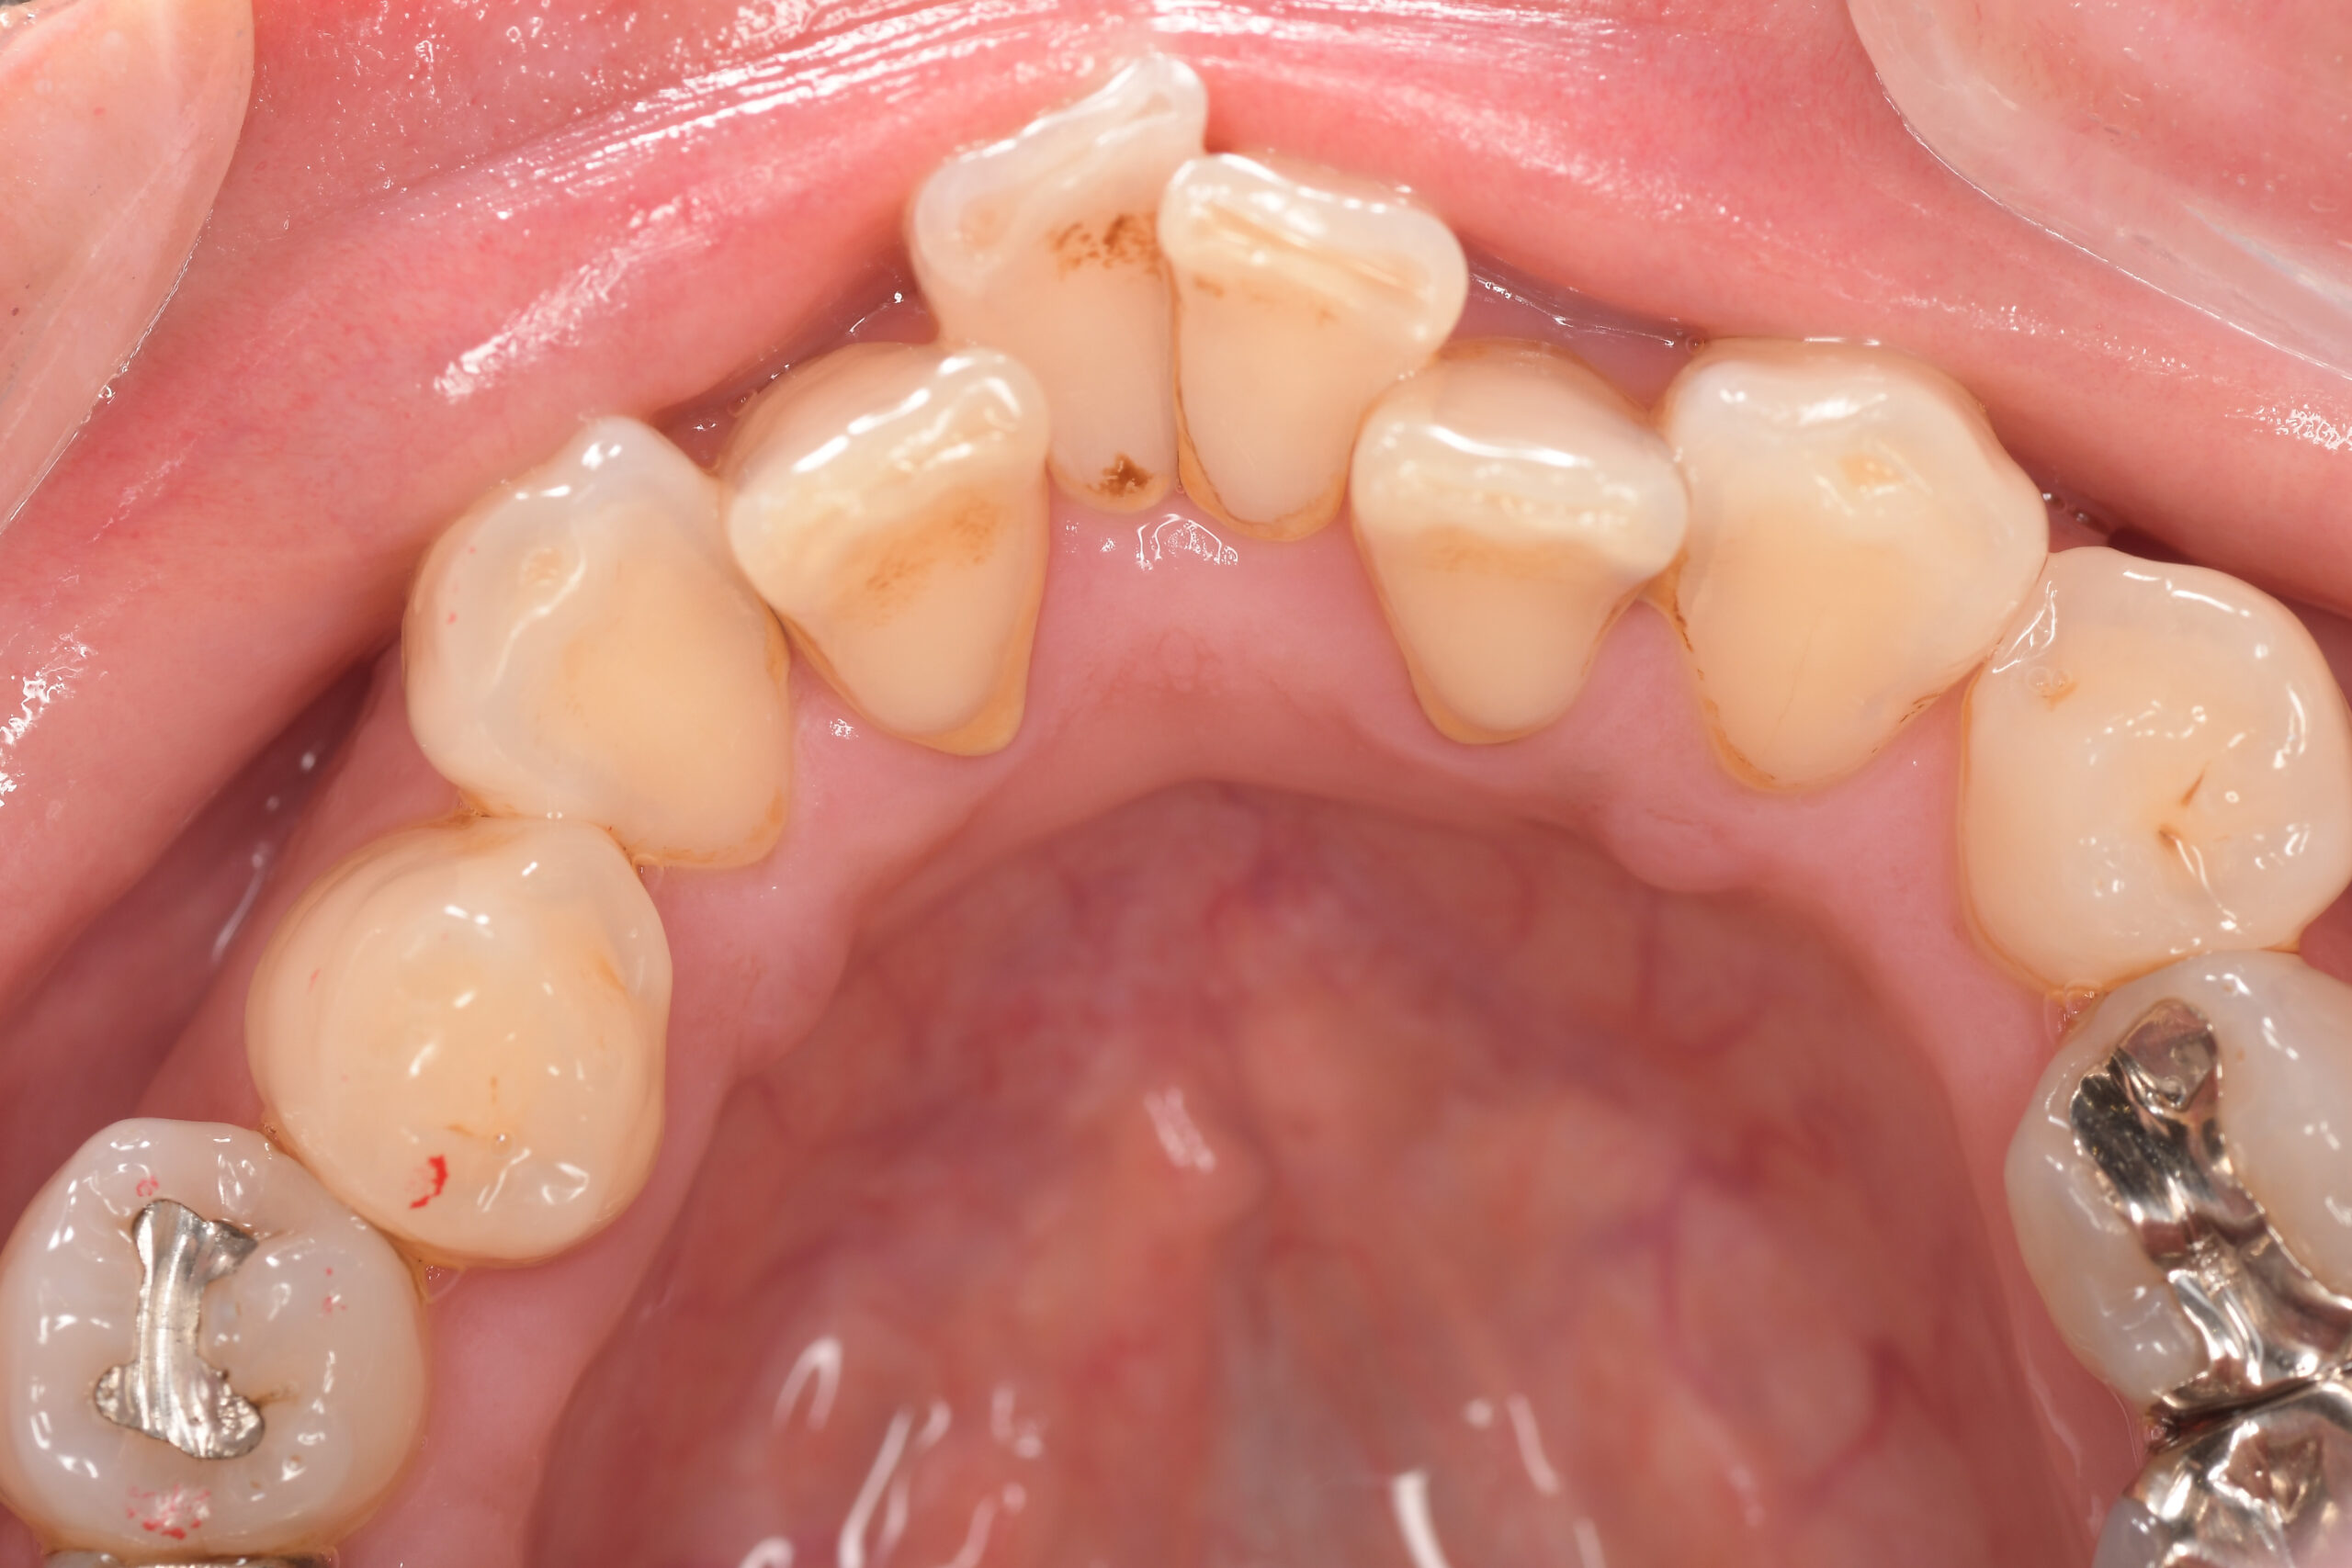

CASE 3

Before

After

基本情報

| 年齢・性別 | 30代・女性 |

|---|---|

| 主訴 | 定期検診 |

| 治療内容 | PMTC |

| 治療期間 | 60分 |

| 治療費 | 5,750円 |

| リスク・副作用 | しみる可能性があります。 |

| 治療方針 | PMTCでステインの除去。 |

| 担当者所見 | ステインが付きやすいため、3カ月毎の定期検診で除去する。 |